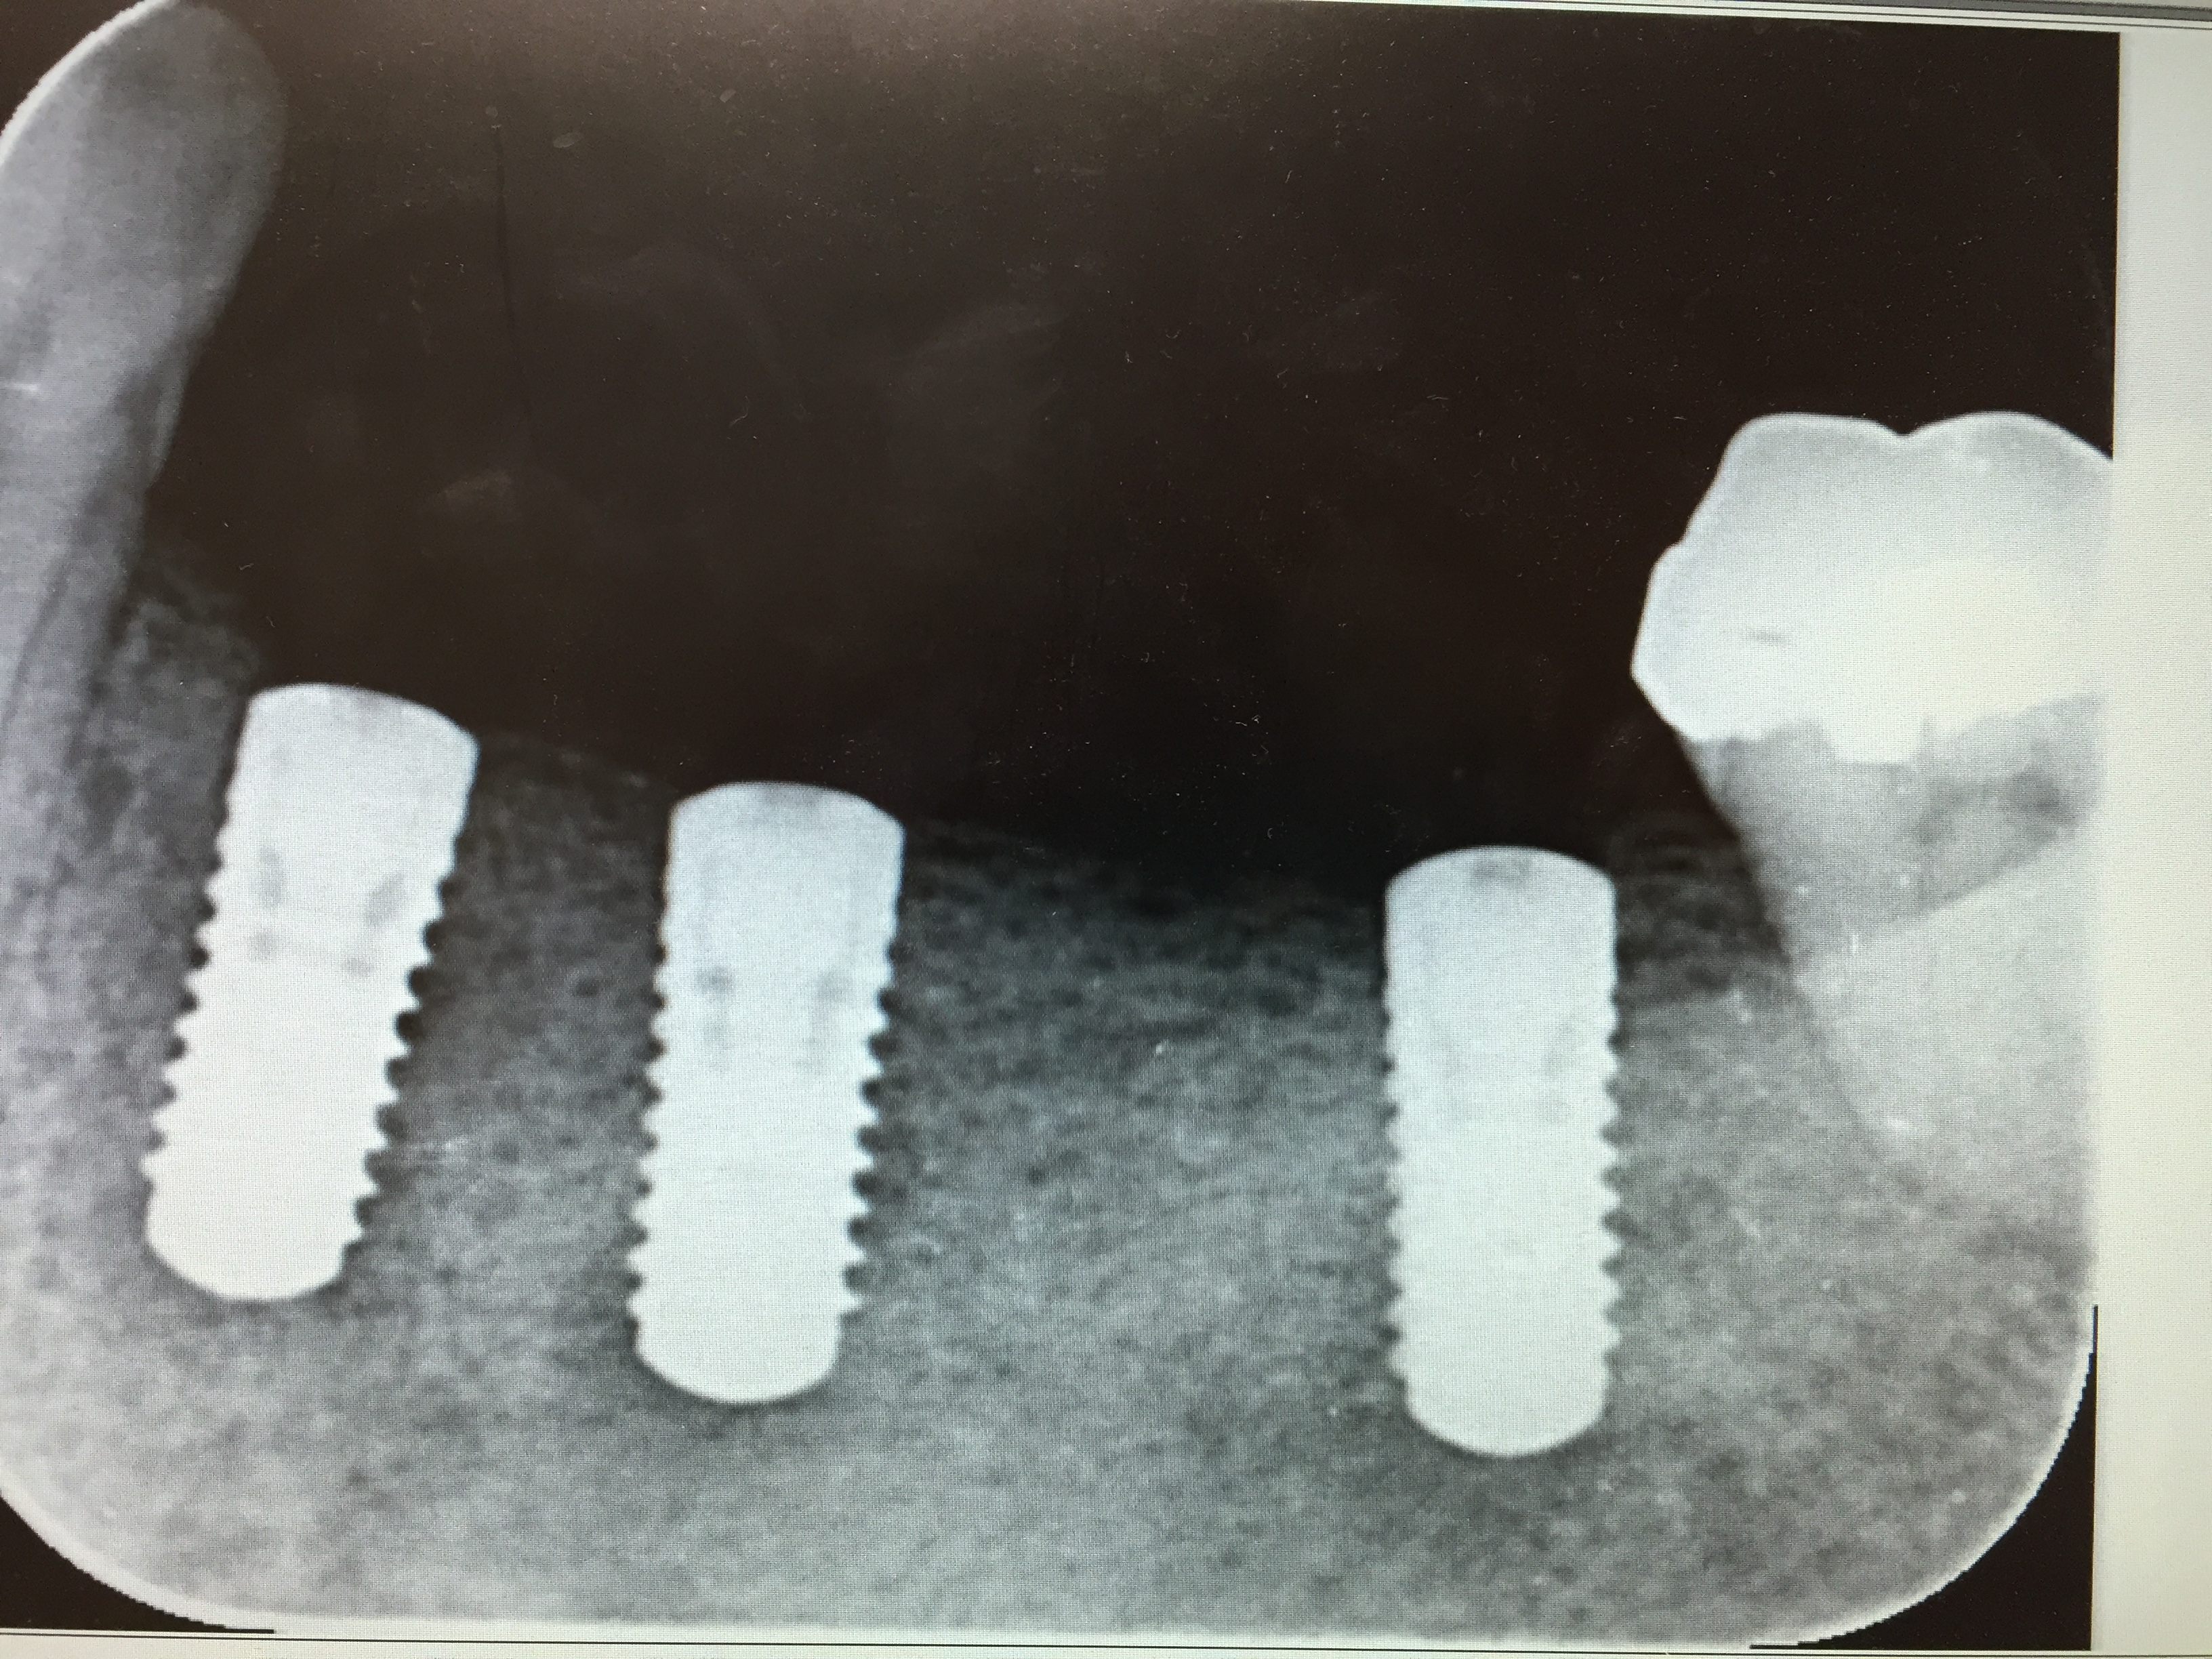

歯の欠損はインプラント治療で回復

歯を失えばその後に控えている治療としては義歯、ブリッジ、インプラント治療もしくはなにもやらないという4つの選択肢があります。

今回はインプラント治療を選択しました。長年義歯の生活から解放されたいということでした。今の入れ歯を使いながらインプラント治療はできます。

義歯の歯のない部分にインプラント手術で入れ込んだあとに義歯の床のピンク色の部分を削って義歯が使えるようにします。3カ月経過後にインプラント部分の歯型をとって完成した時に義歯の使用を中止するので歯が全くなくなってしまう期間はゼロです。